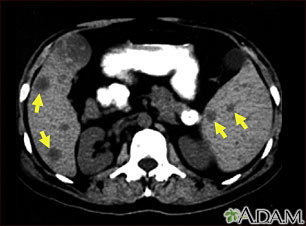

This CT scan of the upper abdomen shows multiple tumors in the liver and spleen that have spread (metastasized) from an original intestinal cancer (carcinoma).